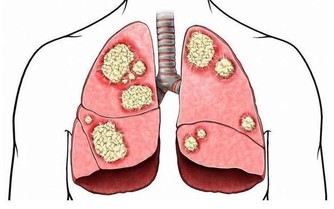

多酚抗癌,類黃酮減少發炎作用

百香果富含的植化素,譬如類胡蘿蔔素以及多酚等,都有助於使癌細胞變得衰弱,可說是絕佳的抗癌食品。讓百香果呈現金黃色澤的,則是類黃酮的成分,類黃酮具有很好的消炎作用,可有效防止並改善過敏、牙周炎和痘痘、粉刺等問題。